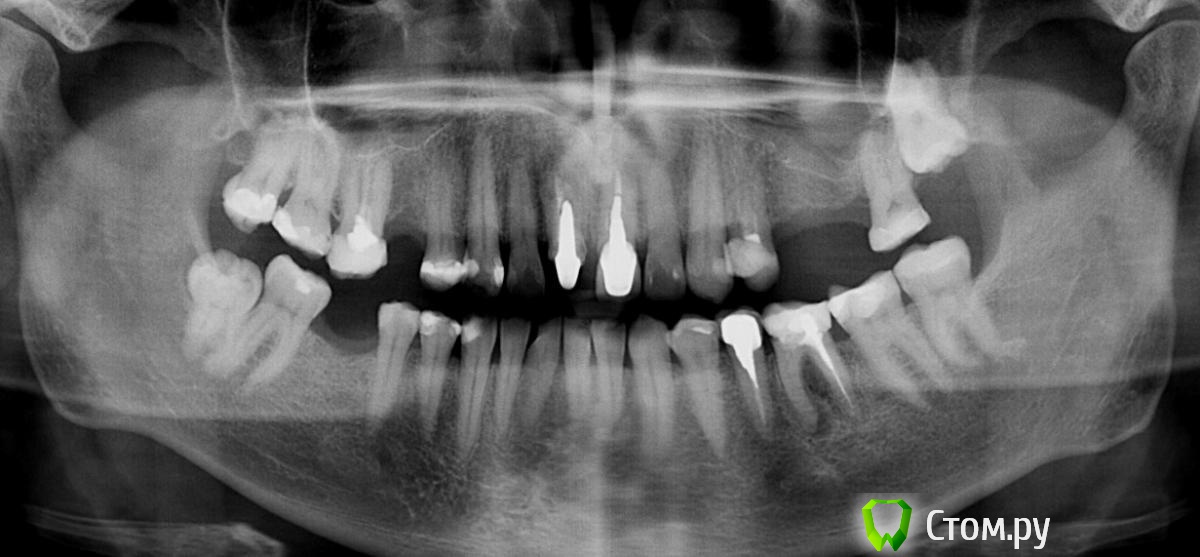

Andex Опубликовано 3 февраля, 2014 Поделиться Опубликовано 3 февраля, 2014 Приветсвую. Коллеги, есть такой случай. Сразу хочу сказать - интерестно обсудить только планирование в области 25-26 зубов. Про остальные "зубки" все понятно. Планирую имплантацию с закрытым синусом в области в позиции 25 и 26 зубов. Но есть одно "НО" - киста на щечном корне 24 зуба. Зуб никогда не беспокоил. Кисту нашел случайно-на 3Д. И вот теперь мысли - сильно ли я рискую, оставив все так как есть(просто проведя операцию), тк с одной стороны-киста нисчем не сообщается(с пазухой), с другой-это явный фактор риска при имплантации. Еще рассматриваю вариант - сделать одновременно с имплантацией цистэктомию апекса щечного корня 24, тк все равно буду отслаиватся в этой области - в таком случае, мои риски понизятся? Сразу скажу - удалять 24 не хочу. Спасибо за интерестные мнения) Ссылка на комментарий

Igor3252 Опубликовано 3 февраля, 2014 Поделиться Опубликовано 3 февраля, 2014 Это не киста , а маленькая гранулемка. Терапевт я думаю получит хороший результат . Синус поднимите в области шестерки. Имплант в 8-10мм вполне справится в позиции 5 зуба . Я бы так сделал Ссылка на комментарий

syrovovec Опубликовано 3 февраля, 2014 Поделиться Опубликовано 3 февраля, 2014 А где киста?небольшая гранулемка только если.. Ссылка на комментарий

Andex Опубликовано 5 февраля, 2014 Автор Поделиться Опубликовано 5 февраля, 2014 А сколько вы хотите поднять на закрытом в обл. 26 и какой длины имплантат собираетесь испольовать?Хотел бы поднять на 3 мм, имплант 4.2х10 Ссылка на комментарий

Andex Опубликовано 5 февраля, 2014 Автор Поделиться Опубликовано 5 февраля, 2014 Хороший ретрит думаю исправит состояние зуба 2.4Почему не хотите открытый синус проводить?Терапевт не взялась за перелечивание. Открытый не хочу, тк считаю что 4мм и 7 мм собственной кости вполне достаточные показания для закрытого, и после него сам сплю спокойнее,чем после открытого) Ссылка на комментарий

bullbull Опубликовано 12 февраля, 2014 Поделиться Опубликовано 12 февраля, 2014 Терапевт не взялась за перелечивание. Открытый не хочу, тк считаю что 4мм и 7 мм собственной кости вполне достаточные показания для закрытого, и после него сам сплю спокойнее,чем после открытого)7 мм - да. 4 мм - сомнительно. Закрытым методом можно поднять на 4, максимум 5 мм.Может дело в финансовой составляющей для пациента? Ссылка на комментарий